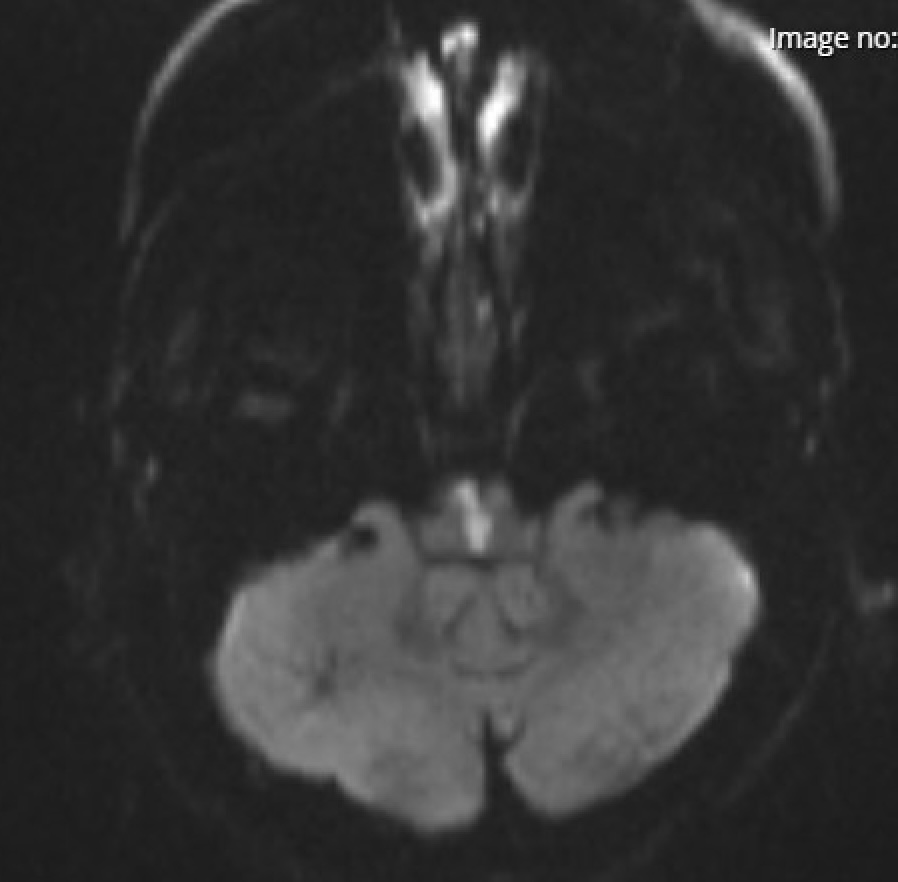

• MRI with diffusion-weighted imaging (DWI) typically shows diffuse cortical and deep gray matter restriction in severe cases.

• EEG may reveal burst suppression or generalized slowing, and somatosensory evoked potentials can assist in prognosis.

• Initial CT head is unremarkable, but MRI performed on day 3 shows diffuse cortical diffusion restriction.